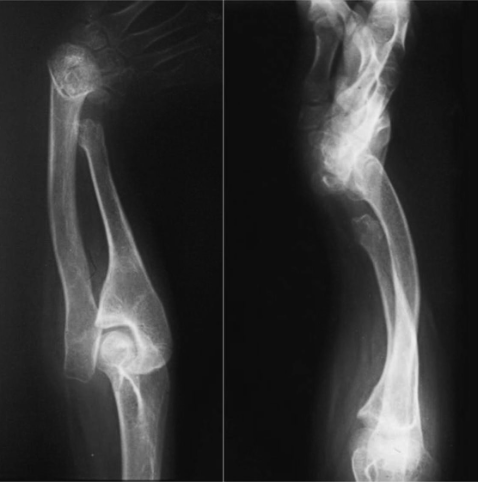

Case 7

The seventh patient was a 13-year-old girl with type 3 deficiency (partial aplasia of the central and distal diaphysis of the ulna) of the affected right arm. The patient had a functional extremity, a normal hand, and a stable wrist and elbow. Radiographs showed partial aplasia of the ulna involving the middle and distal diaphysis with a hypoplastic distal metaphysis and epiphysis. There was negative ulnar variance but no deficiencies of the wrist and hand. The proximal part of the ulna was not hypoplastic, and the radius was straight (Figure 7).